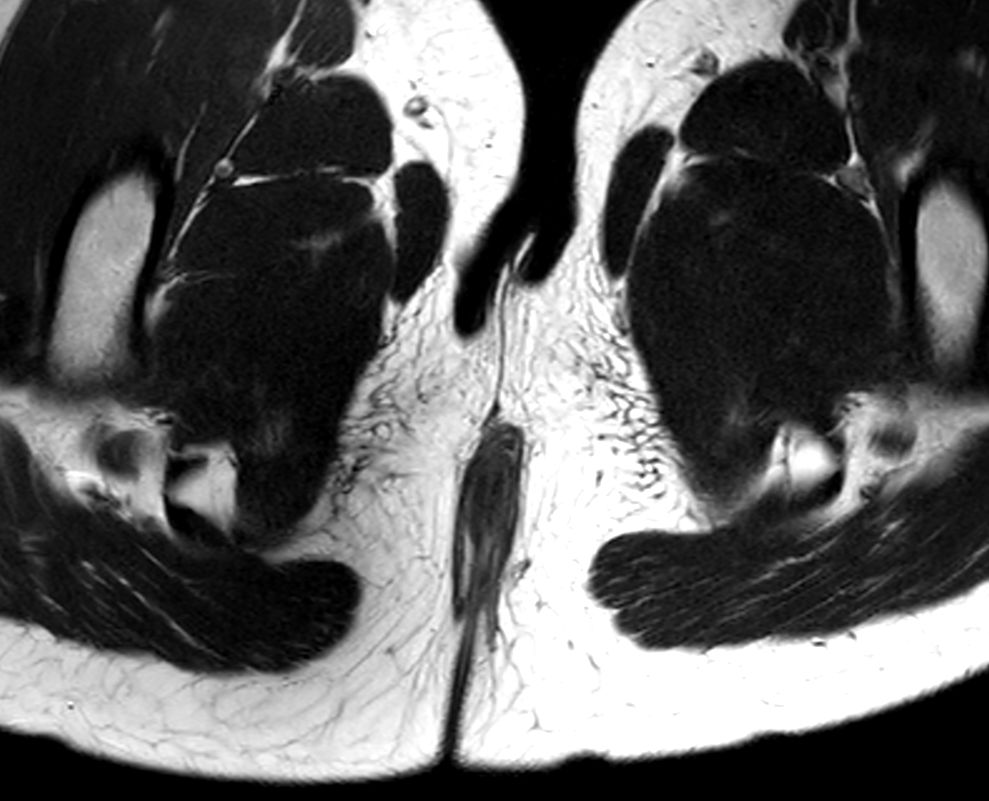

8 years old pediatric patient with a fistula in the pelvis. MultiVane XD is used to achieve high resolution diagnostic images, even in the case of severe patient motion. Integration of Compressed SENSE acceleration technique enables speeding up of the entire exam.

Axial T2w TSE Compressed SENSE